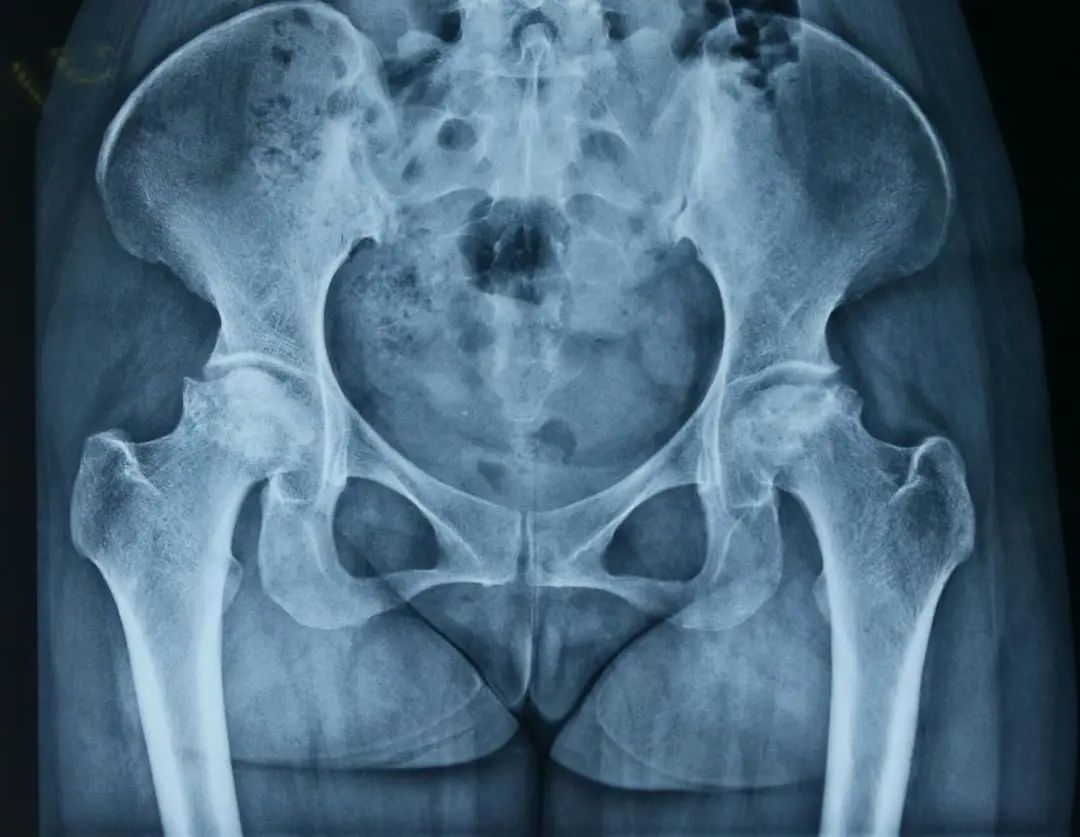

术前平片

章先生,男,65岁,因双侧髋关节疼痛伴活动受限10余年入院,章先生此前因医疗信息获取困难、家住偏远山区就医困难等因素一直忍受髋关节疼痛,多次于当地基层医疗机构予以止痛药口服、草药外敷等保守治疗后无明显好转,决定来瑞安人民医院关节外科门诊就诊,刘敏主任予完善双髋X片检查,判断其双髋关节股骨头坏死程度较重,结合章先生严重的临床症状,考虑手术指征明确,建议章先生手术治疗。章先生经过考虑后,克服内心对手术的恐惧与顾虑,最终同意手术。

经过全髋关节置换手术,以及术前术后医护人员的精心护理,章先生最终获得了满意的手术及预后效果,在术后第2天,章先生便可以自主下地行走,他也对医护人员表示了由衷的感谢,解决了他十余年的疼痛顽疾。